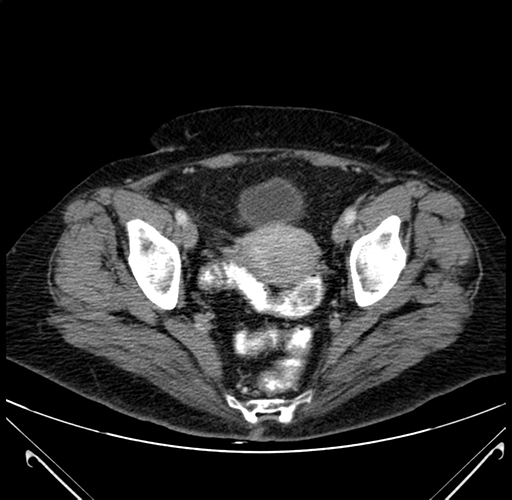

Axial Venous